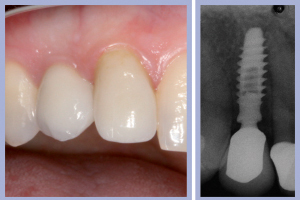

La valutazione clinica al momento della consegna dei manufatti e clinico-radiologica a 3 mesi dalla consegna manifestava una completa integrazione tissutale con eccellente recupero estetico e funzionale (Figg. 29-30).

- Figg. 29a, b Manufatti di destra e radiografia di controllo. Si noti l’ottima integrazione tissutale

- Figg. 30a, b – Manufatti di sinistra e radiografia di controllo